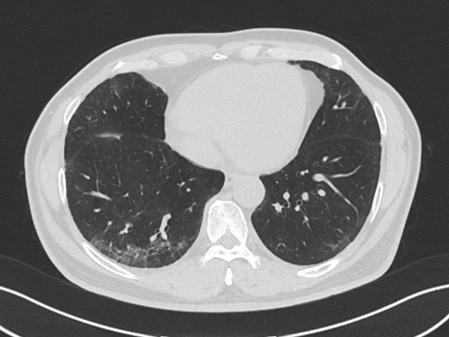

病例1:患者,男,60歲,因“咳嗽、活動(dòng)后氣促7個(gè)月”于2024年7月25日求診我院?;颊咴?個(gè)月內(nèi)先后4次就診其他醫(yī)院住院治療,均被診斷為“肺炎”,但治療后癥狀沒有改善,氣促反而加重。轉(zhuǎn)診我院后,間質(zhì)肺規(guī)范化診療中心主任張宏英經(jīng)詢問病史,患者從事木頭加工,考慮電鋸木粉吸入導(dǎo)致過敏性肺炎,經(jīng)影像科、病理科等多學(xué)科協(xié)助,最終確定了診斷:木屑所致的非纖維化型過敏性肺炎,治療不到1周,恢復(fù)出院。

過敏原無處不在,但又很隱匿,宿主的易感性也不一樣。過敏性肺炎早發(fā)現(xiàn)、脫離環(huán)境就可以治愈,但是由于患者經(jīng)常未及時(shí)發(fā)現(xiàn)過敏原,對(duì)于早期肺部比較典型的影像特征也缺乏足夠的敏感性,仍繼續(xù)暴露在過敏環(huán)境中,最后發(fā)展成纖維化型過敏性肺炎。我院間質(zhì)肺規(guī)范化診療中心將盡可能詳盡地采集病史以發(fā)現(xiàn)可能存在的環(huán)境暴露因素以及時(shí)間軸關(guān)系,發(fā)揮多學(xué)科診療優(yōu)勢(shì),早發(fā)現(xiàn)早診斷,助力患者盡快脫離過敏原,避免不可逆的肺纖維化。

1.分類:按照是否存在影像和(或)病理學(xué)的肺部纖維化表現(xiàn),分為非纖維化型過敏性肺炎和纖維化型過敏性肺炎。

3.自然病程和預(yù)后:過敏性肺炎的自然病程差異很大,從好轉(zhuǎn)、進(jìn)行性惡化、呼吸衰竭、死亡均可出現(xiàn)。非纖維化性型過敏性肺炎在避免抗原暴露后病情可能穩(wěn)定或痊愈,但纖維化型過敏性肺炎,特別是表現(xiàn)為尋常型間質(zhì)性肺炎(UIP)的患者生存期短,文獻(xiàn)報(bào)道 30%-50% 的患者未能確定致敏原,隱匿的長(zhǎng)期接觸致敏原可能導(dǎo)致纖維化型過敏性肺炎。